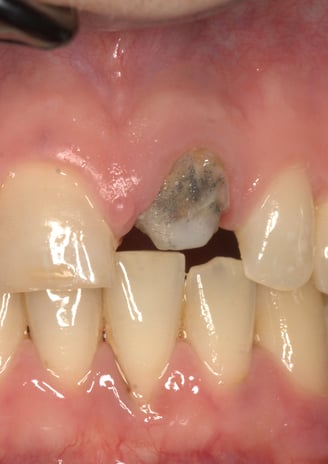

Trattamento endodontico inadeguato: il precedente trattamento canalare era insufficiente, lasciando il dente vulnerabile a infezioni e compromettendone la prognosi a lungo termine.

Perno moncone inadeguato: la mancanza di stabilità del perno esistente causava la continua decementazione della corona, rendendo necessario un intervento risolutivo.

Moncone non ritentivo

Trattamento Canalare Incongruo

2. Sostituzione del Perno Moncone

Il perno moncone preesistente è stato rimosso e sostituito con un perno in fibra di vetro. Questo materiale offre vantaggi significativi:

Elasticità simile alla dentina naturale, riducendo il rischio di fratture radicolari.

Elevata adesione ai materiali compositi, garantendo una maggiore stabilità della ricostruzione.

Radiotrasparenza, permettendo un migliore controllo radiografico nel tempo.